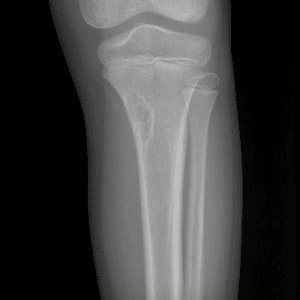

Pediatric Radiographs